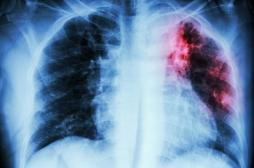

tuberculose